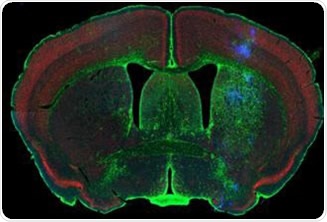

3-D micrometer scale tomography has been enabled by the use of optical sections and can be used to create high-resolution maps of small, stained rodent brains, including the depiction of associated neurons and corresponding processes. Clear images with improved optical resolution (especially in the depth direction), can also be produced using confocal fluorescence techniques where out-of-focus light from the sample that is outside the focal plane is eliminated via a pinhole.

Figure 1. Rodent brain (top) depicting simultaneous acquisition of fluorophores Cy2, Cy3 and Cy5; Brain image (bottom) magnified to 0.5 μm. Image credit: Huron Digital Pathology.

- This is the only confocal fluorescence digital slide scanner that enables the simultaneous acquisition of up to three fluorophores spanning the whole visible spectrum, from 400nm-850nm. This provides considerable time-savings and less photo bleaching due to the unique flying-spot laser platform.